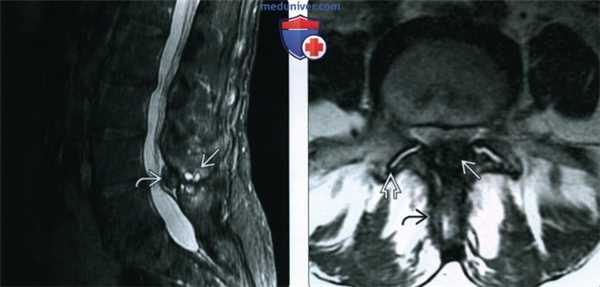

(Слева) МРТ, корональная проекция, режим протонной плотности: признаки ОА, включая полную утрату хряща, субкортикальный склероз и верхние краевые остеофиты. Определяется истончение сухожилия надостной мышцы. На других срезах визуализировались признаки полнослойного разрыва вращательной манжеты. Выпот визуализируется как в плечевом суставе, так и в подакромиально-поддельтовидной сумке.

4. МРТ при остеоартрозе плечевого и локтевого суставов:

• Режим Т1:

о Сигнал низкой интенсивности: субхондральные кисты, субхондральный склероз

о Крупные, зрелые остеофиты отличаются наличием сигнала, характерного для костного мозга

о При наличии крупного остеофита нижневнутреннего отдела головки плечевой кости используйте режим Т1 в сагиттальной и аксиальной плоскостях для оценки сближения с подмышечным нервом в четырехстороннем отверстии

• Последовательности, чувствительные к жидкости:

о Сигнал низкой интенсивности: субхондральный склероз

о Сигнал высокой интенсивности: отек костного мозга, субхондральные кисты

о Для синовита характерно утолщение с сигналом низкой интенсивности, граничащее с высоко интенсивным выпотом,

о При наличии выпота осуществляйте поиск фокальных дефектов хряща или его диффузное истончение

о Сопутствующий разрыв сухожилия или тендинопатия

о Нейропатия, характеризующаяся сигналом высокой интенсивности:

- ОА плечевого сустава: подмышечный нерв в четырехстороннем отверстии

- ОА локтевого сустава: локтевой нерв в кубитальном канале

(Слева) МРТ, сагиттальная проекция, режим Т2: признаки ОА локтевого сустава от легких до умеренных, включая остеофиты и легкое истончение хряща.

(Справа) МРТ, сагиттальная проекция, режим Т2: ОА сочленения между головкой лучевой кости и головкой мыщелка плечевой кости со свободными телами в растянутом заднем завороте. Признаки остеофитоза визуализируются сзади. Также имеются признаки субхондрального склероза и утраты хряща. Визуализация мелких свободных тел при МРТ или рентгенографии затруднена.